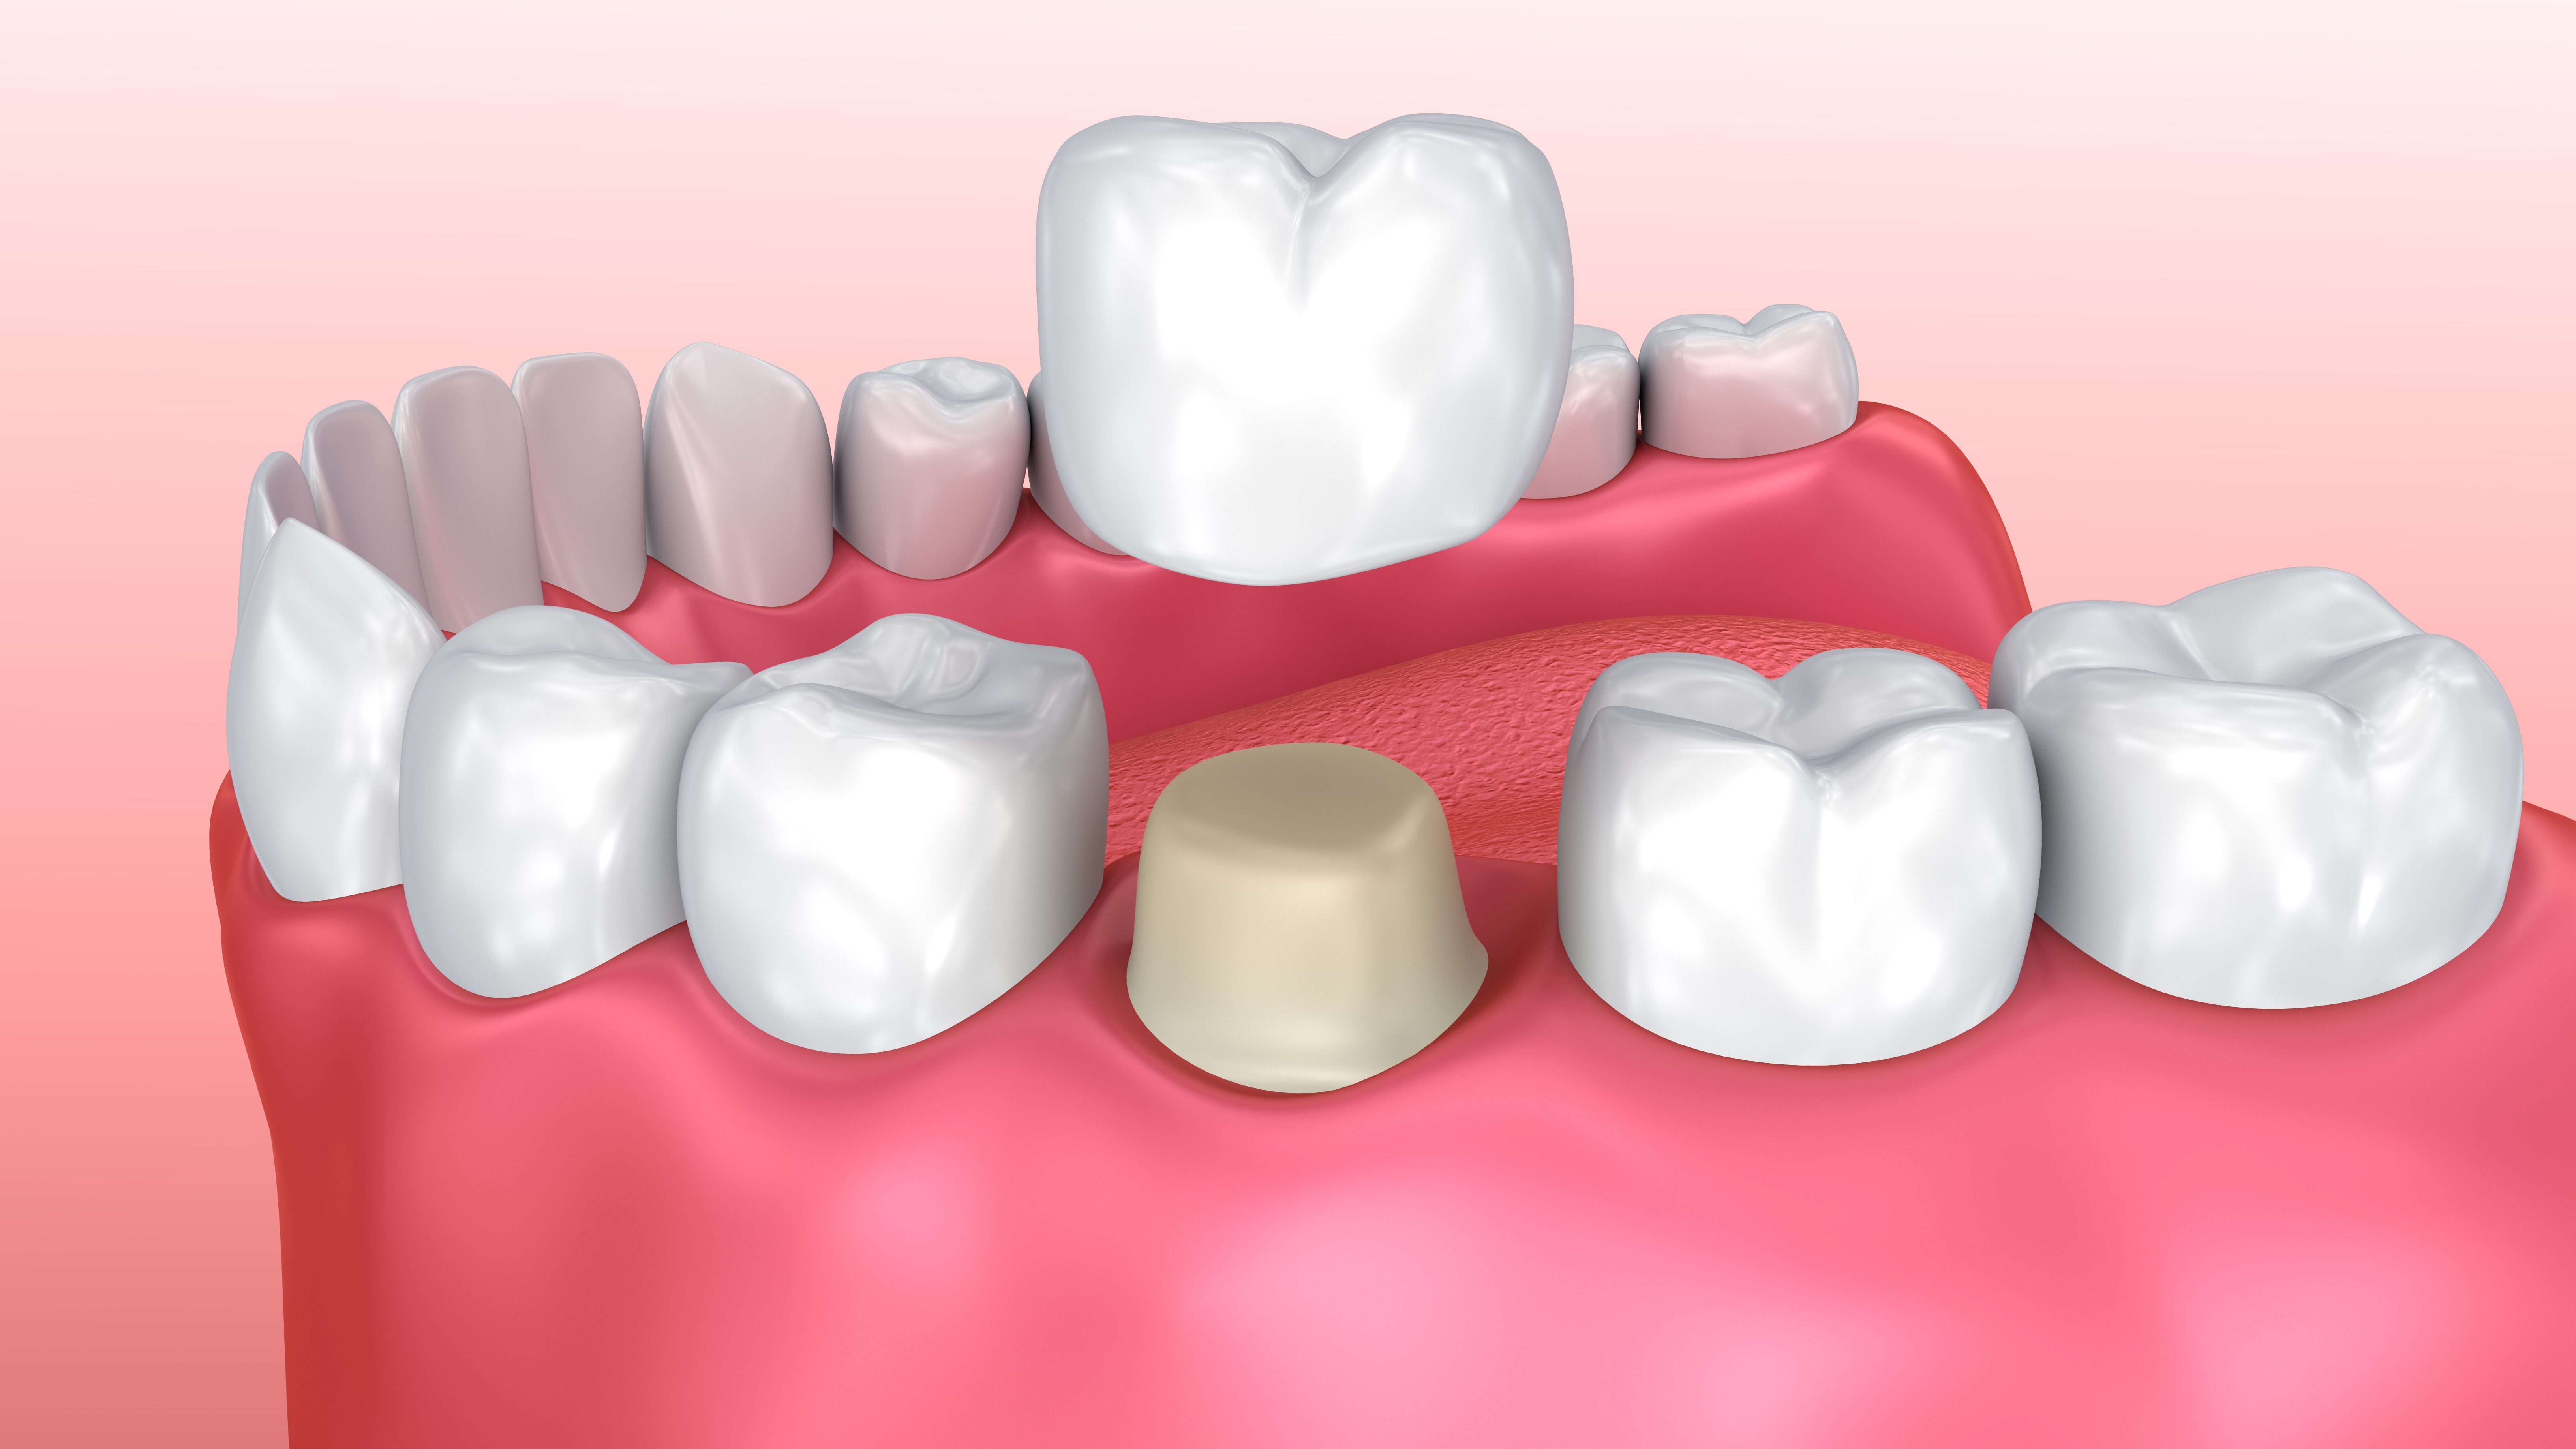

Couronnes

Nous réalisons au cabinet dentaire des couronnes en céramique (Nous n’utilisons plus de métal qui est contraire à l’évolution des matériaux dans notre profession). L’indication de réalisation d’une couronne est souvent la réfection d’une plus ancienne. Notre leitmotiv sera la préservation au maximum de l’organe dentaire ; C’est ainsi que dès que possible nous préfèrerons réaliser des facettes sur les dents antérieures, ou des onlays/overlays sur les dents postérieures.